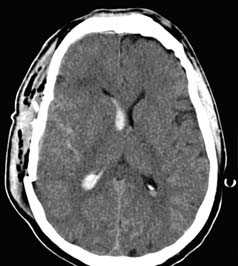

а - Типичные ушибы мозга лобной и височной локализации (стрелки).

б - Геморрагический ушиб правой височной доли (двойная стрелка) с выраженным перифокальным отеком (одинарные стрелки). A-В «Растущие» бифронтальные ушибы у 47-летнего алкоголика. Даты проведения исследований указаны на изображениях. а - Компьютерная томография при диффузном аксональном повреждении.

Многочисленные геморрагические очаги (стрелки), расположенные вдоль средней линии, а также правосторонняя лобновисочная эпидуральная гематома.